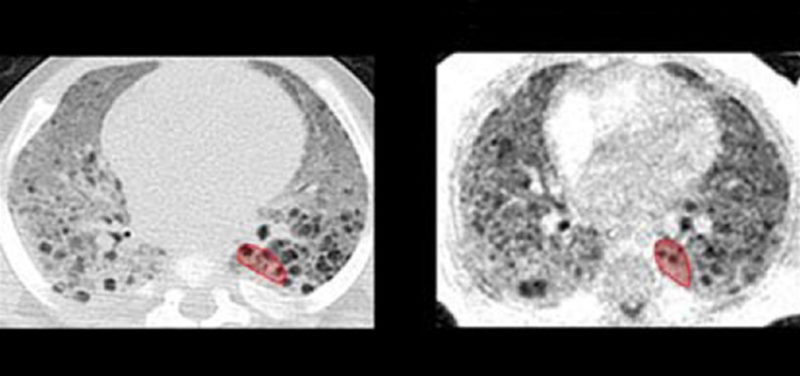

Figure 1: Slice-matched images comparing clinical CT scans (left column) and research UTE MRI scans (right column) in five diseased subjects (from top to bottom: Subjects A through E). CT and MRI exams were typically performed at different time points for each individual subject; chronological ages at each subject’s CT and MRI exams are provided.